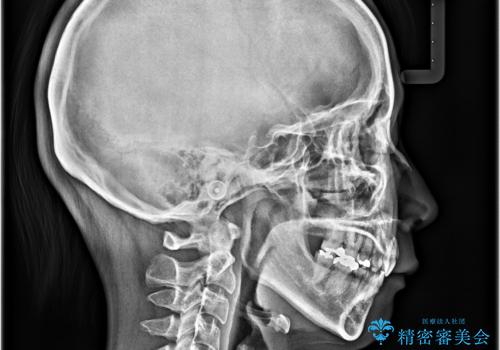

顎先に梅干し皺ができる 閉じにくい唇を抜歯矯正で閉じやすく

- 口元の突出感と口の閉じにくさを気にして来院された患者様です。

上下左右第一小臼歯4本を抜歯し、ワイヤー装置にて口元を引っ込めるよう矯正治療を行うこととしました。

奥歯が前方に傾斜していることで深く咬みこむ(ディープバイト)状態であったので、なかなか抜歯したスペースが閉じず、様々な方法でディープバイトを改善しながら治療を進めていくこととなりました。